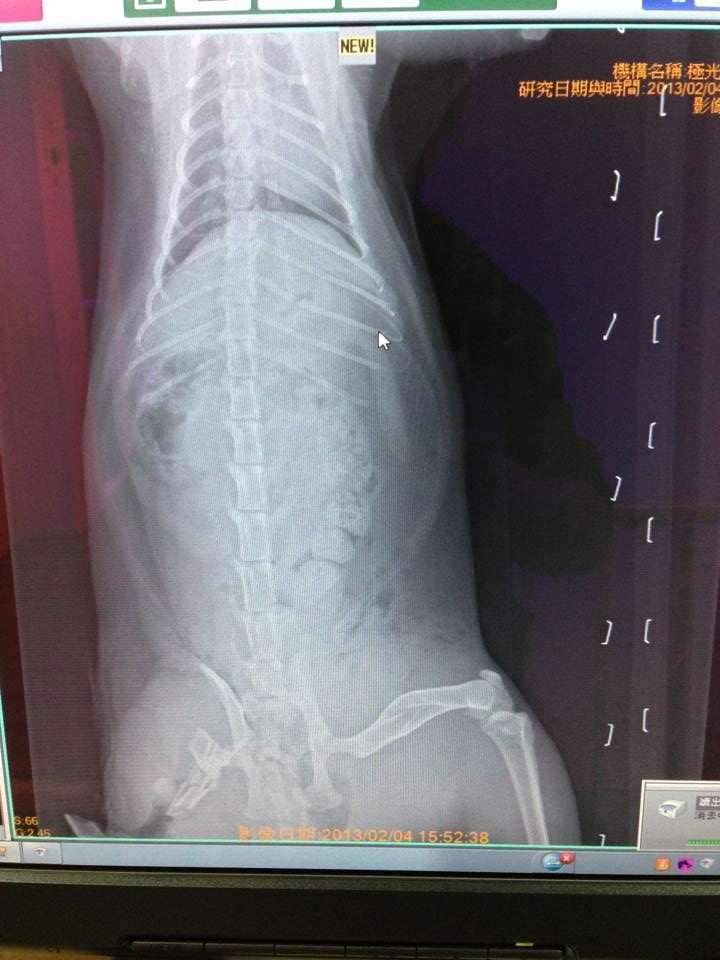

在2月初的中午,麥可出門被車撞了!

她拖著兩條受傷的腿,

趕緊爬回這她唯一認定的家!

麥克到院前已奄奄一息、呼吸急促…

經醫師通知告知麥克的後腿撞斷、動脈與神經受損,

只怕後腿不保…